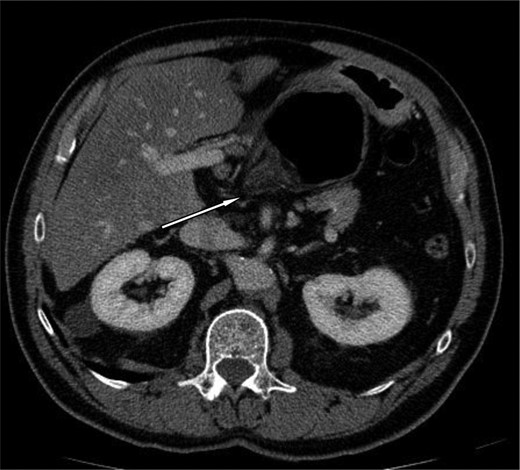

A 69-year-old patient presented to our emergency room with progressive dull abdominal pain and distension without nausea, vomiting or change in bowel habits. Physical examination showed pain with moderate guarding in the right upper and lower quadrants. A plain abdominal X-ray and a CT scan were performed. Radiological findings suggested the diagnosis of an internal hernia through the epiploic foramen and containing the right colon with important distension of the caecum (Fig. 1). Surgical exploration was then performed using an open approach. At laparotomy, we found an internal herniation of the caecum and the entire ascending colon through the foramen of Winslow (Figs 2 and 3). After hernia reduction, multiple patchy areas of caecal necrosis were observed (Fig. 4). A formal right hemi-colectomy was therefore performed. The postoperative recovery was uneventful.

Axial section through upper abdomen showing distended caecum with air-fluid level (A) with the displacement of the stomach (B) laterally.